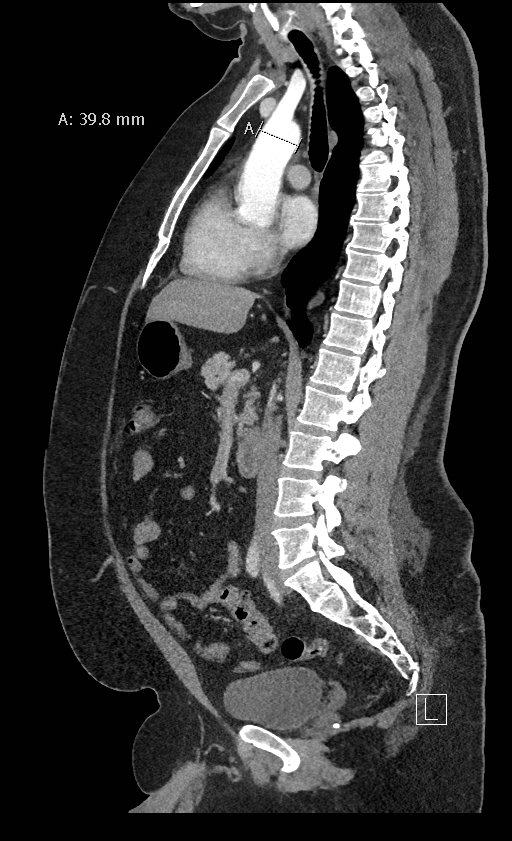

Point-of-care cardiac echocardiogram demonstrated a dilated ascending aorta (illustrated in red) measuring approximately 4 cm in the parasternal long axis (PLAX). A dilated aortic arch (illustrated in green) also measuring approximately 4 cm was appreciated using the suprasternal notch view (SSNV). A follow-up computed tomography angiogram (CTA) was performed, validating bedside ultrasound measurements.

The diagnostic criteria for dilated thoracic aneurysm is based on multiple factors including age, sex, and body size.2 An aortic root diameter of ³ 4.0 cm constitutes an ascending aortic dilation.3,4 Point-of-care cardiac and SSNV ultrasound of the thoracic aorta has been validated as an accurate study when performed by emergency physicians to identify thoracic aortic aneurysms (sensitivity of 71.4%, specificity of 100% when compared to gold standard of CTA). 5 This case is an example of the utility of rapid bedside diagnostic ultrasound, specifically the SSNV, in assessment of thoracic aneurysms.